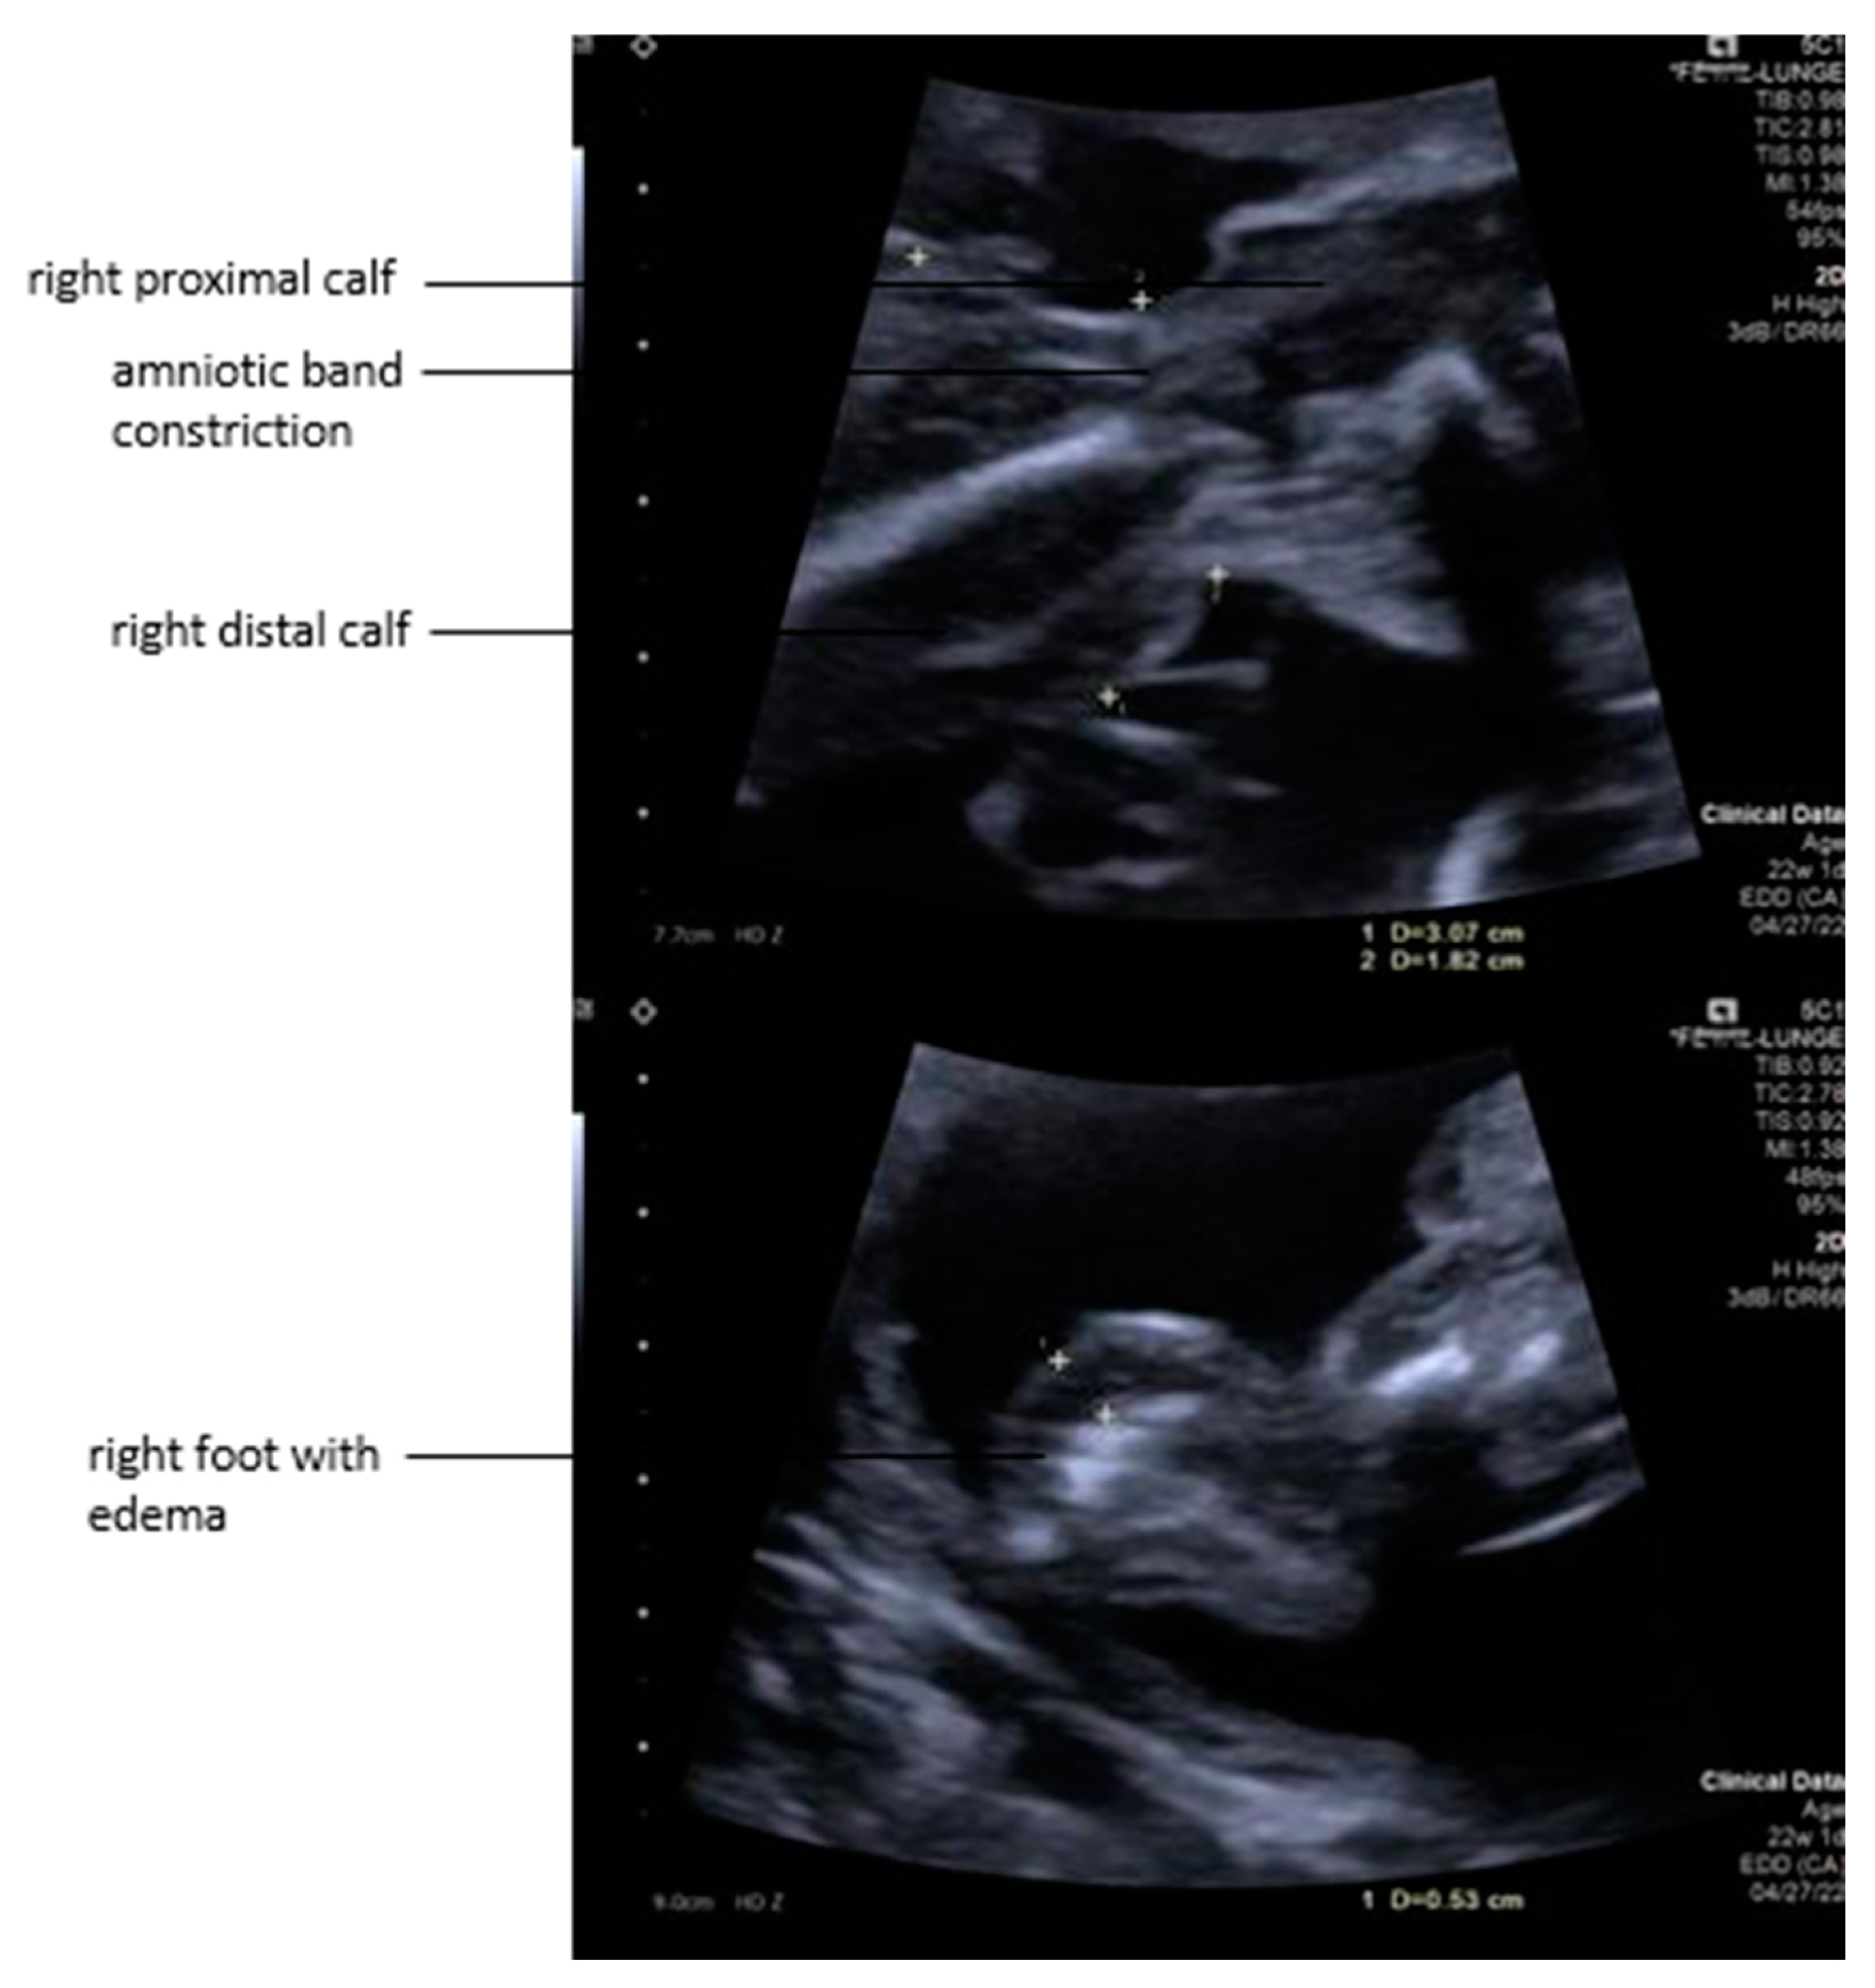

Several loops of the umbilical cord were entangled in amniotic tissue and parts of the abrupted placenta. Due to localized entrapment of umbilical cord slings and increased umbilical venous blood flow velocities, a constriction of the umbilical cord was suspected. Strangulation of the right calf was also noted, with associated edema extending down to the foot (Figure 2). A Doppler ultrasound assessment of the right leg indicated that the fetus might benefit from amniotic band removal as it showed decreased venous blood flow distal to the constriction, heralding the risk of limb loss without prompt intervention. Furthermore, the left leg protruded through the abrupted placental segment.

Figure 2. Top: The fetal right calf was strangulated by an amniotic band with distal limb edema due to the constriction. Bottom: The right foot became severely enlarged from the development of edema.